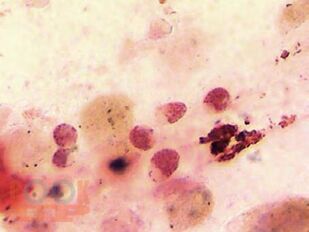

В монографии изложены представления о кислотных протравных антрахиноновых красителях, их свойствах, механизмах взаимодействия с биомолекулами. На примере эритроцитов периферической крови, клеток надпочечников и соединительной ткани продемонстрирован гистохимический метод окраски с применением ализаринового красного С бихроматом калия, в качестве протравы, с оценкой флуоресценции. Учитывая представленные структурные особенности микроскопических препаратов и гистохимической реакции для выявления флуоресценции с применением антрахиноновых протравных красителей, монография будет интересна для врачей патологоанатомов, биологов, специалистов в области гистологии, клеточной биологии, биохимии, физиологии и патофизиологии.